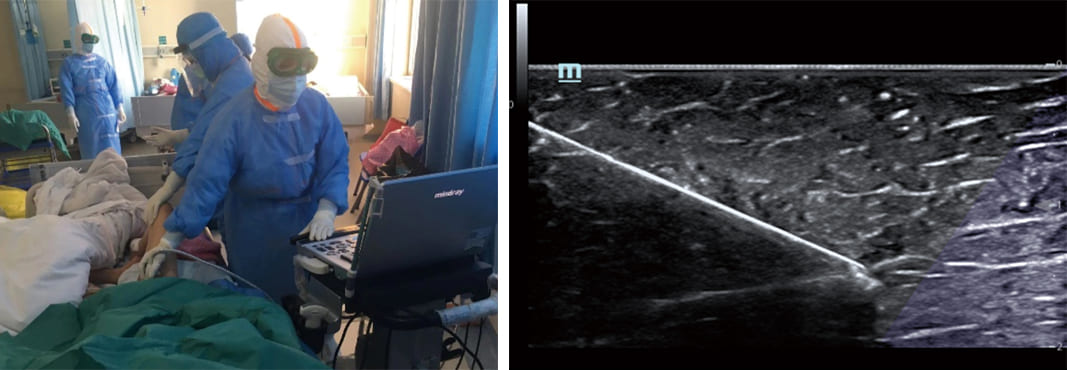

5. iNeedle and iTouch Functions

Portable ultrasound devices come with additional features like iNeedle and iTouch, further enhancing their utility. The iNeedle function assists clinicians in puncture procedures. This needle enhancement function provides real-time guidance during punctures, increasing precision and minimizing the risk of complications. On the other hand, the iTouch feature simplifies the optimization of images. With a single touch, clinicians can quickly optimize image quality, improving the diagnostic accuracy and efficiency of the ultrasound.

uis-in-critical-care-fig5